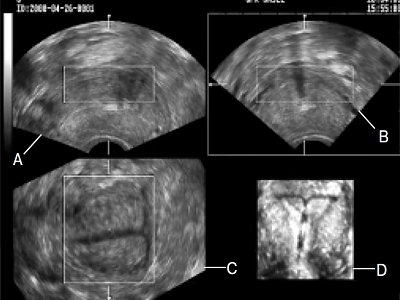

Полученное объемное изображение внутриматочного средства в полости матки вращали в трех плоскостях с получением стандартных планов: вид А представлял поперечный срез, вид В - продольный срез, С - фронтальный (рис. 1). На фронтальном срезе стало возможным получить полное представление о структуре вертикальной оси контрацептива с резервуаром со стероидами и горизонтальными ветвями.

А - поперечный вид, В - продольный вид, С - фронтальный вид.

б) Увеличенное фронтальное изображение.

Позади него визуализировалась акустическая тень с так называемым "миражем" внутриматочного средства (рис. 2). До настоящего времени этот феномен описывался лишь при получении продольного среза между концами вертикальной оси в обычном двухмерном режиме [1].